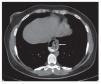

Las etiologías más comunes de la falla son la recurrencia de hernia hiatal (Figuras 1, 2a y 2b) y la disrupción de la funduplicatura,15 que combinadas representan entre el 50 y el 65%. Causas menos comunes son: Malposición de la funduplicatura, funduplicatura apretada y cierre crural ajustado. Incluso se han reportado casos de acalasias que no habían sido identificadas previamente por la decisión de realizar funduplicatura inicial sin manometría.11,12,14

¿ Figura 2a.Tomografía de tórax en la que se observa herniación de la funduplicatura (flecha) al tórax.